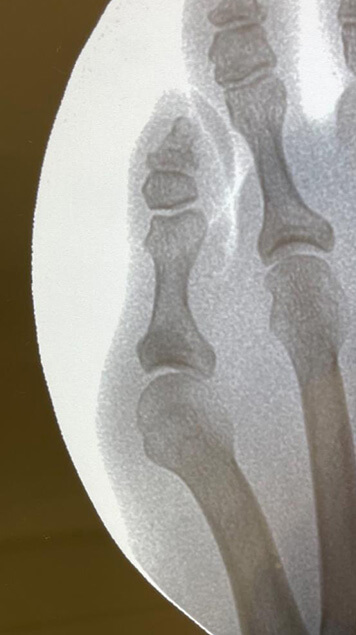

Radiografía de juanete de sastre o bunionette.

Hellerhoff (2020) CC BY-SA 4.0

El juanete de sastre es una deformidad que se caracteriza por una prominencia ósea en la base del quinto dedo del pie, causada por

la desviación del quinto metatarsiano hacia fuera y el quinto dedo hacia dentro.

Esta prominencia puede ser dolorosa, especialmente al roce con el calzado.

En la imagen se puede apreciar la prominencia en el quinto dedo característica del juanete de sastre.